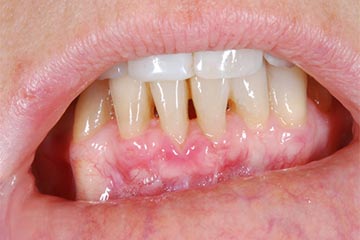

Lembo libero per correggere una recessione gengivale